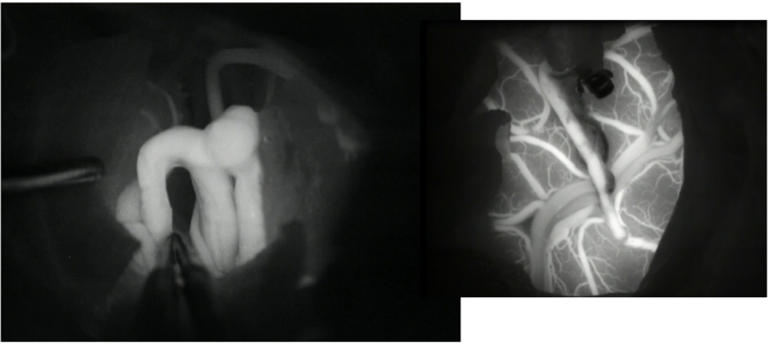

A dynamic contrast-enhanced MRI study highlighted the pituitary microadenoma (Fig 1). Inferior petrosal sinus sampling confirmed an ACTH- secreting pituitary adenoma on the left side (peripheral ACTH – 11.6pg/ml, right IPS- 26.9, left IPS – 44).

Figure 1. Coronal section, T1 weighted post-contrast dynamic sequence image of the pituitary fossa showing the tumour, a rounded region of delayed enhancement (green arrow) compared to the rest of the gland.

She was counselled for total resection of the tumour through an Endoscopic endonasal approach (EEA). EEA was performed through the right paraseptal route with the left rescue flap using the standard endoscope (Fig. 2). ICG was administered and a custom ICG-integrated endoscope was introduced. The tumour was visualized as appearing non-fluorescent compared with the normal pituitary gland (Fig. 3). The adjourning ICA was also visualized (Fig. 4). A soft whitish tumour was resected after capsulotomy. The anterior and posterior lobes were confirmed and remained fluorescent with ICG. Pseudo capsulectomy was added. After total resection, hemostasis was confirmed and the sellar floor was repaired.

Figure 4: Angiographic view of the parasellar ICA following ICG injection